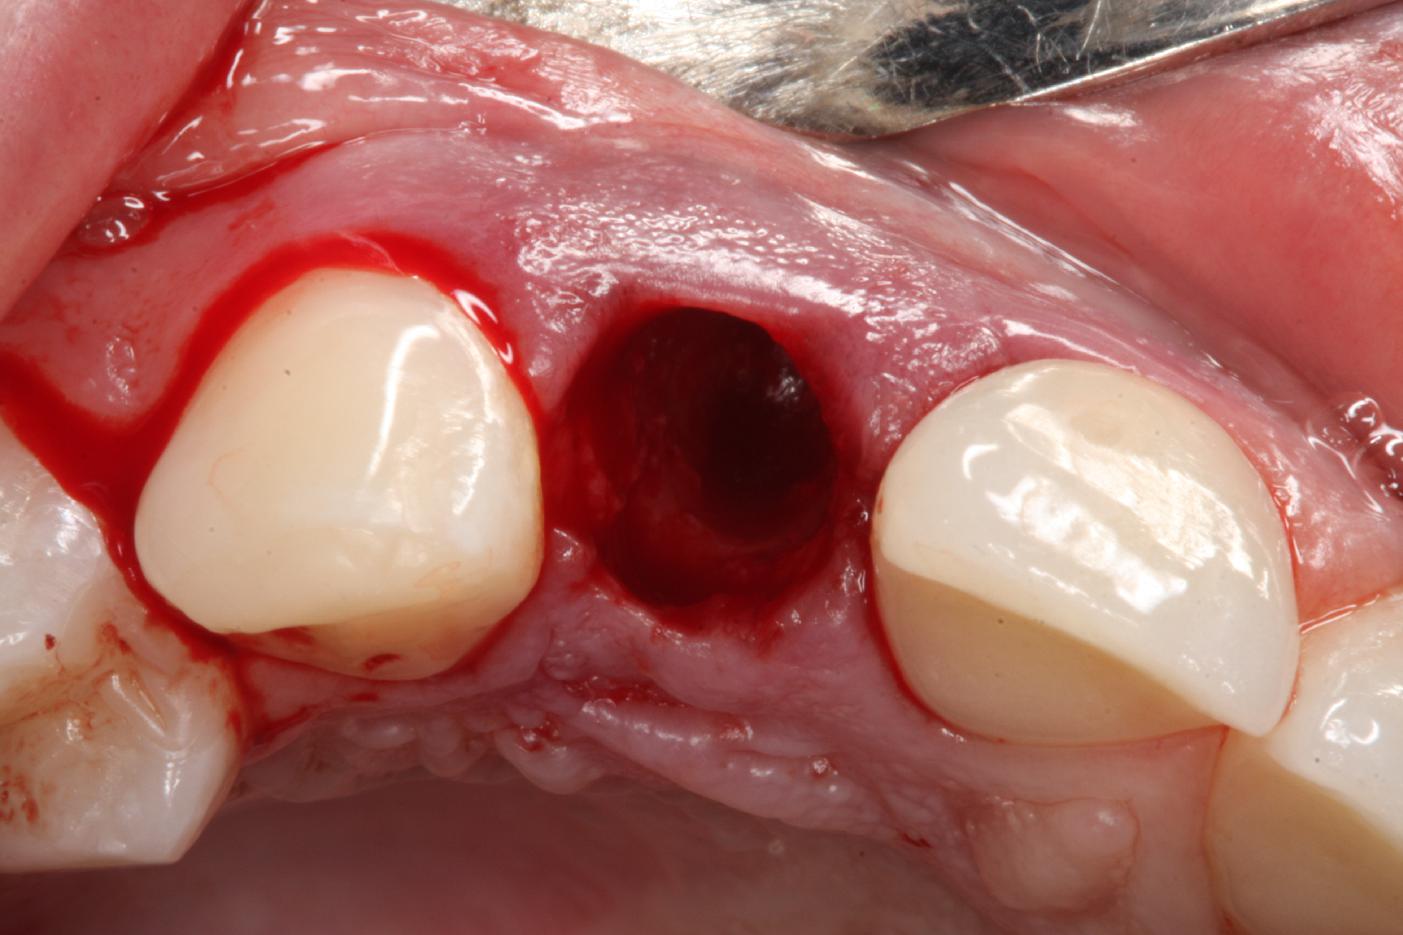

2/12 - Atraumatic tooth extractionSoft tissue thickening at immediate implant placement and GBR with mucoderm® and maxgraft® - Dr. A. Puisys

3/12 - Intact socketSoft tissue thickening at immediate implant placement and GBR with mucoderm® and maxgraft® - Dr. A. Puisys

Intact socket following atraumatic tooth extraction

Tooth extraction due to root fracture